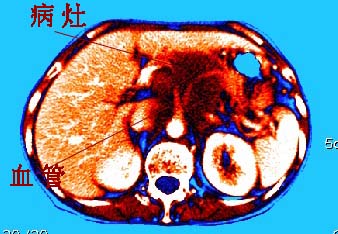

再看从肠系膜根部到胰腺后主动脉及上腔静脉周围可见相连的较大的软组织肿块影,形态不规则,呈明显

的大小不等的分叶状,其中密度较均匀但其中可见条状低密度区,肿块边缘比较清晰周围的小肠受压移位

明显且堆积。

增强所见,腹腔动脉,肠系膜上动静脉被肿块包绕,结合平扫的条状低密度区恰好位于血管周围,较大的

肿块强化不明显(遗憾的是没有标上ct值)但胃壁强化的十分明显。

讨论:首先看肠系膜和腹膜后的肿块我认为是多发融合的肿大的淋巴结。理由1大小不等的分叶,分布比较

自由。2其中的包绕的血管和周围少量的脂肪即所说的。